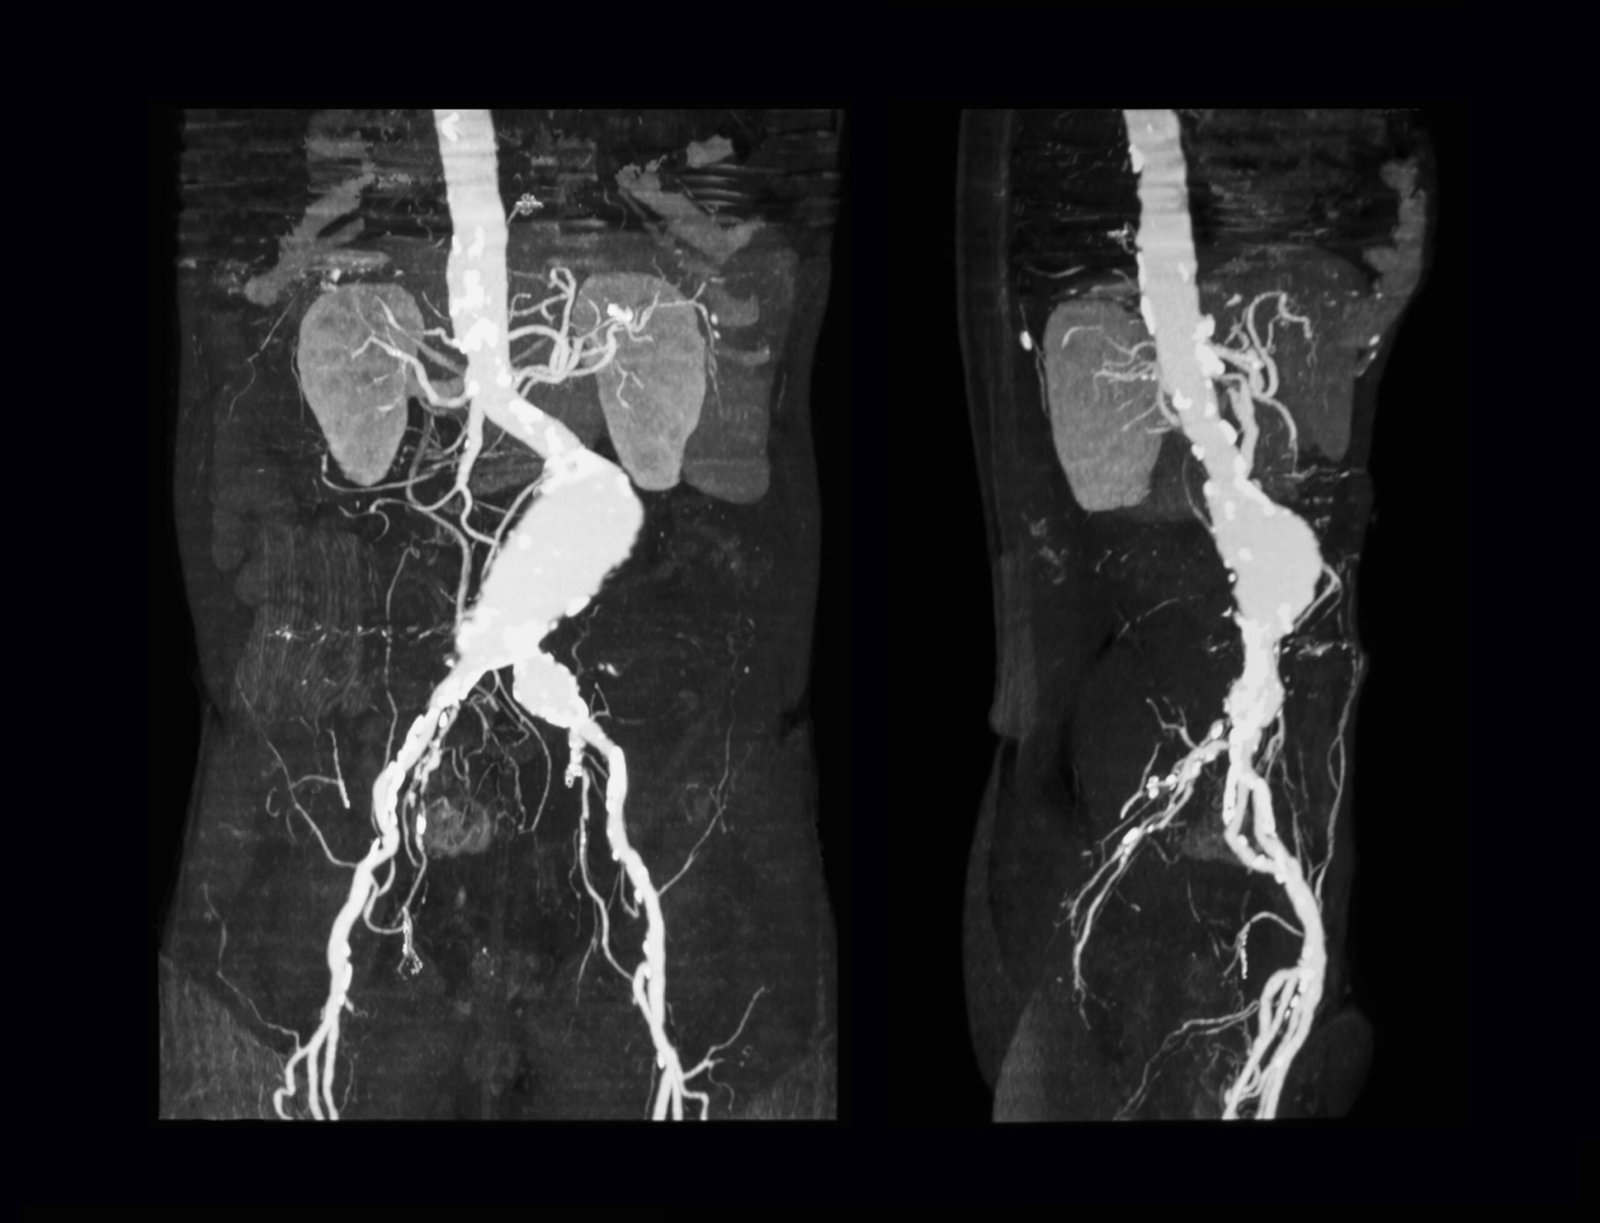

If you are at risk for AAA, or if an aneurysm is suspected, your healthcare provider may recommend an ultrasound or CT scan to assess the size and location of the aneurysm. Regular screening can help detect an aneurysm before it causes symptoms. If the aneurysm is large enough to be a concern, further tests may be required to determine the most appropriate course of action.

We offer state-of-the-art ultrasound and CT imaging services to accurately assess the size and location of any aneurysms. With access to advanced procedures like Endovascular Aneurysm Repair (EVAR) and traditional open surgery, we can offer the most appropriate and effective treatment options available.